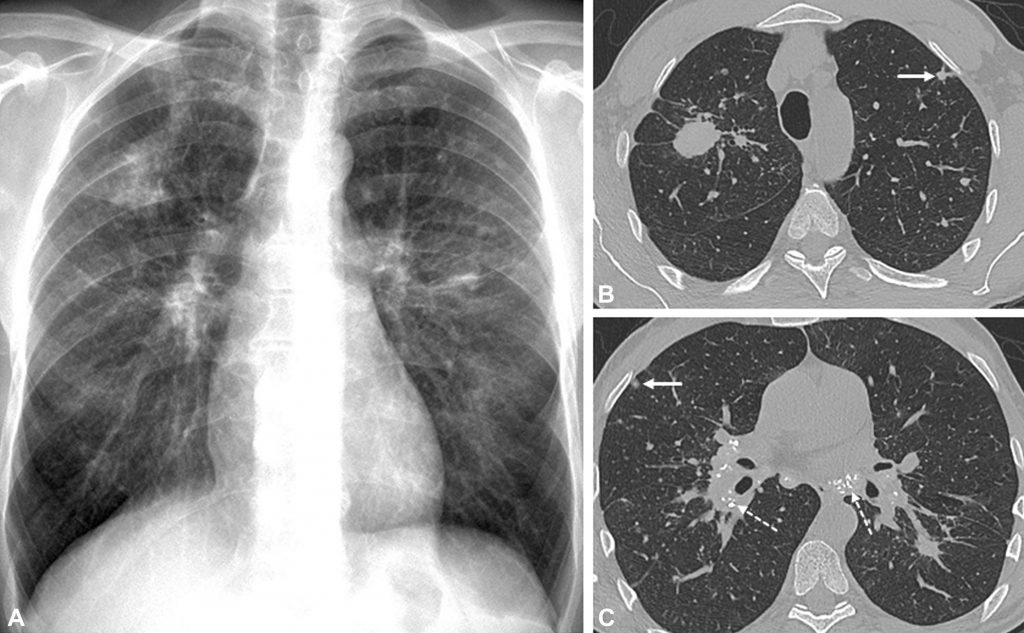

Fig. 95.1. Silicose pulmonaire.

Radiographie de face (A) et coupes TDM (B, C) montrant des opacités macro- et micronodulaires bilatérales prédominant dans les sommets, certaines de topographie sous-pleurale (flèches pleines), accompagnées d’adénopathies calcifiées médiastinales et hilaires (flèches en pointillé).

Source : CERF, CNEBMN, 2022.